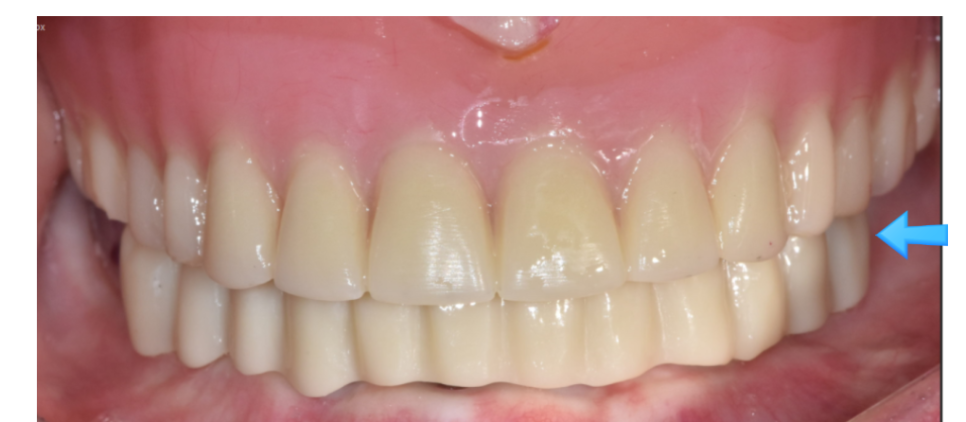

240203 올온포 모습

전체 임플란트보다 덜 부담스럽지만

틀니보다 잘 씹을 수 있고

편하게 쓸 수 있다

3가지만 기억하시면 되실 것 같습니다.